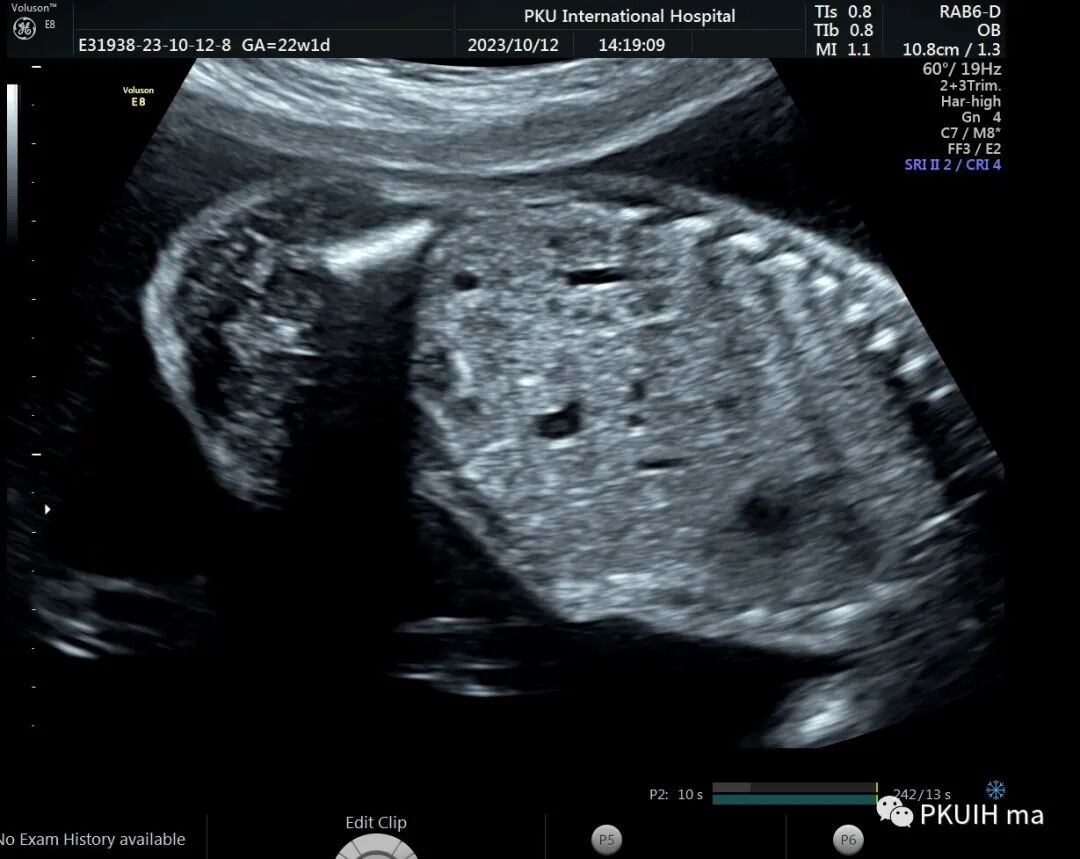

今天看到一22周的胎儿,一侧肾区未见肾脏结构,肾上腺呈平卧征,肾动脉也未显示,在盆腔见到一个发育不良的肾脏回声。

右肾大小位置正常,右肾动脉可见,左肾动脉缺如,正常的左肾区未见肾组织回声,可见肾上腺平卧。于膀胱后上方见一肾组织回声,大小约1.5x1.4x1.0cm,皮髓质分界欠清晰,血供来源于髂动脉。